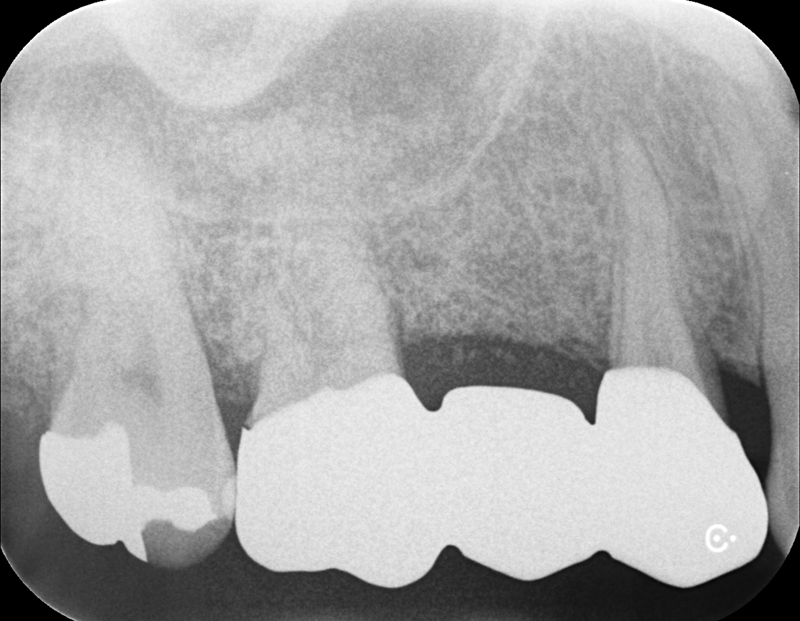

Case3

術前

術中

術後

根面被覆

| 治療名 | 前歯インプラント、根面被覆 |

|---|---|

| 治療説明 | 前歯4本の抜歯が必要となったためインプラントで回復することになりました。右上1,左上1に抜歯と同時にインプラントを埋入しました。右上2、左上2は結合組織移植を行いボリュームを回復することで、見た目と清掃性を向上させました。左右側方歯には根面被覆術を行って歯肉退縮を回復しました。 |

| 治療回数・期間 | 1年 |

| 副作用とリスク | インプラント治療は入れ歯やブリッジと比べて治療期間が長くかかることがあります。インプラント手術と結合組織移植は、違和感、痛み、腫れ、出血などが発生する場合があります。一時的なもので、2日〜1週間で治まります。 |

| 料金(税込) | 骨造成:110,000円(2本:220,000円) インプラント1次手術:220,000円(2本:440,000円) インプラント2次手術:55,000円(2本:110,000円) 結合組織移植:110,000円(4本:440,000円) 上部構造:220,000円(4本:880,000円) 根面被覆:396,000円 合計:2,456,000円 |